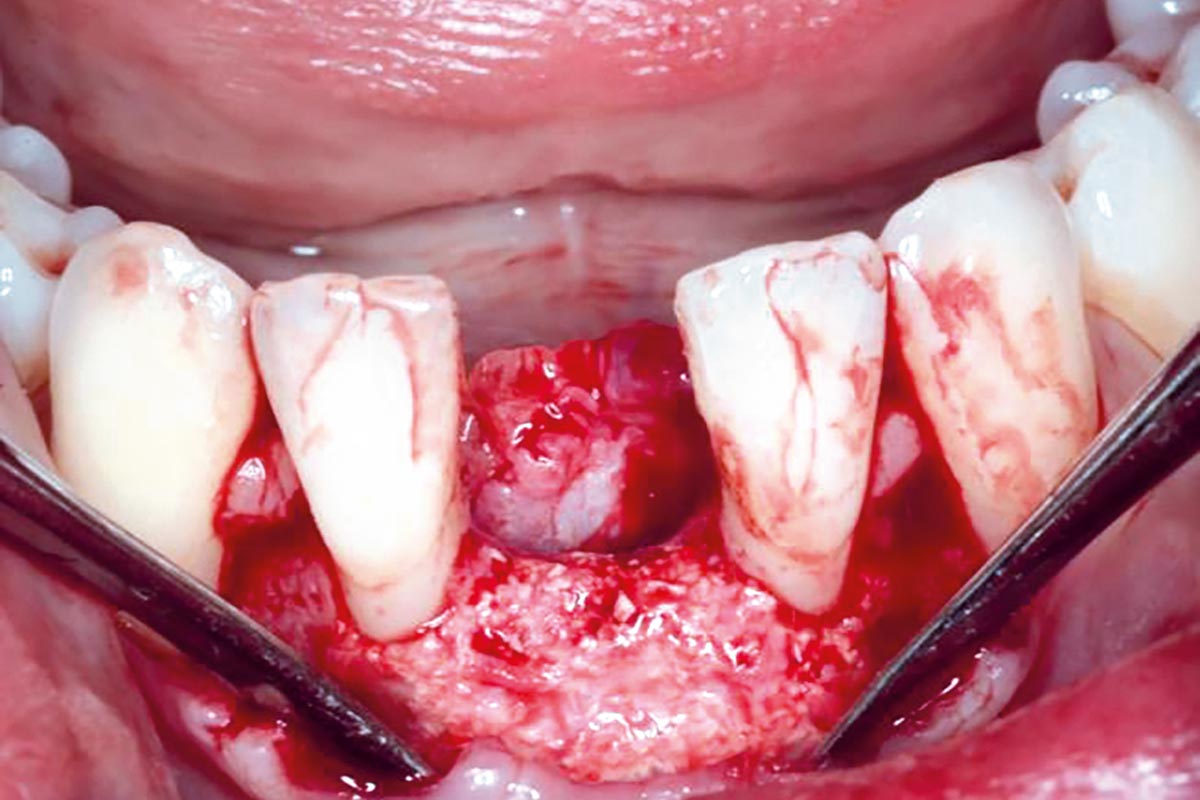

Horizontal GBR in the anterior mandible - Dr. B. Molnar

Clinical situation with narrow alveolar ridge in the lower jaw